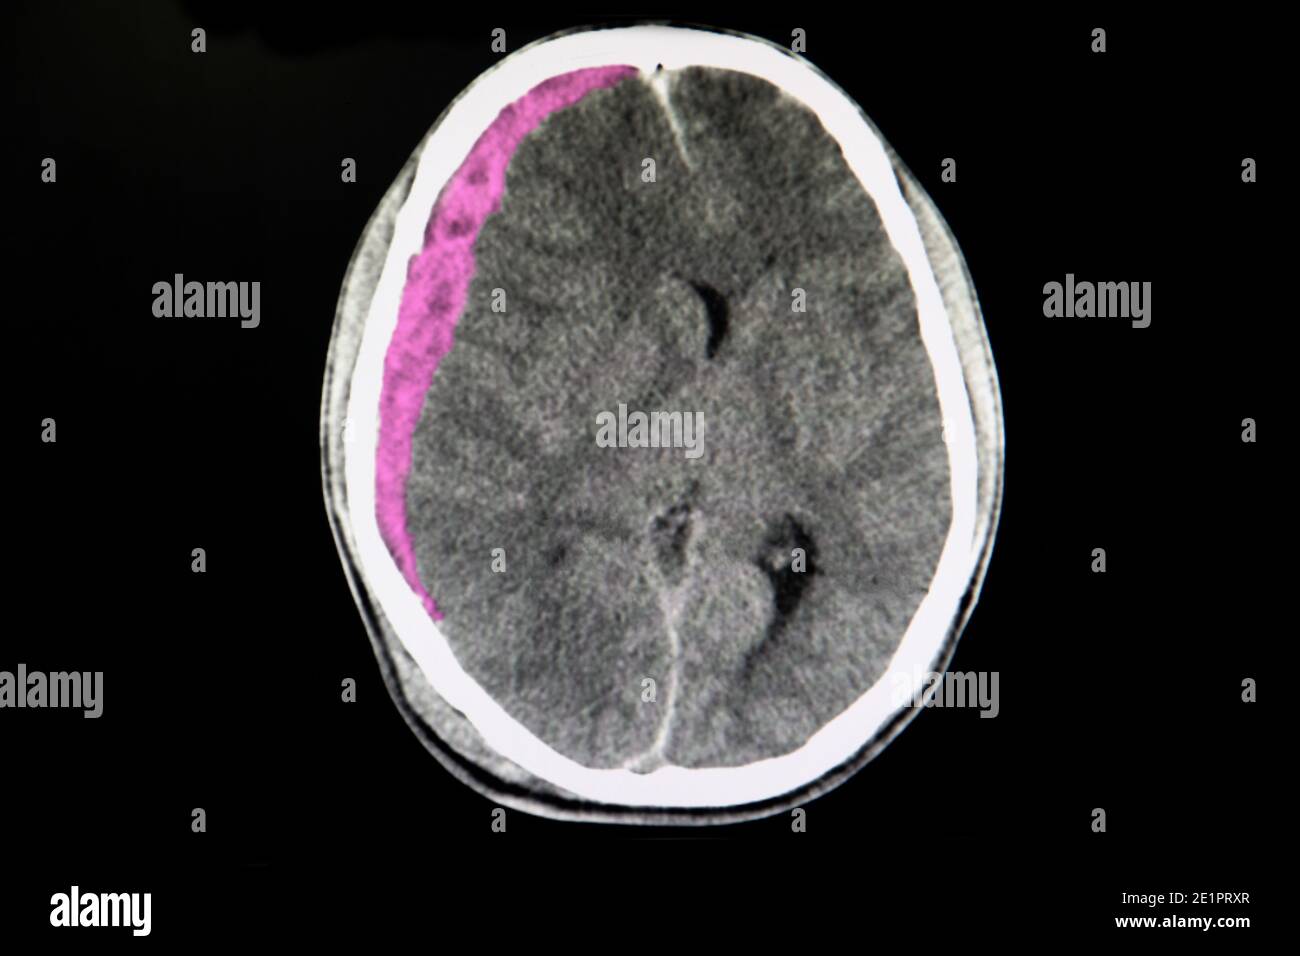

Emorragia Subdurale Con L Edema Del Cervello Fotografia Stock Immagine Di Testa Voluminoso